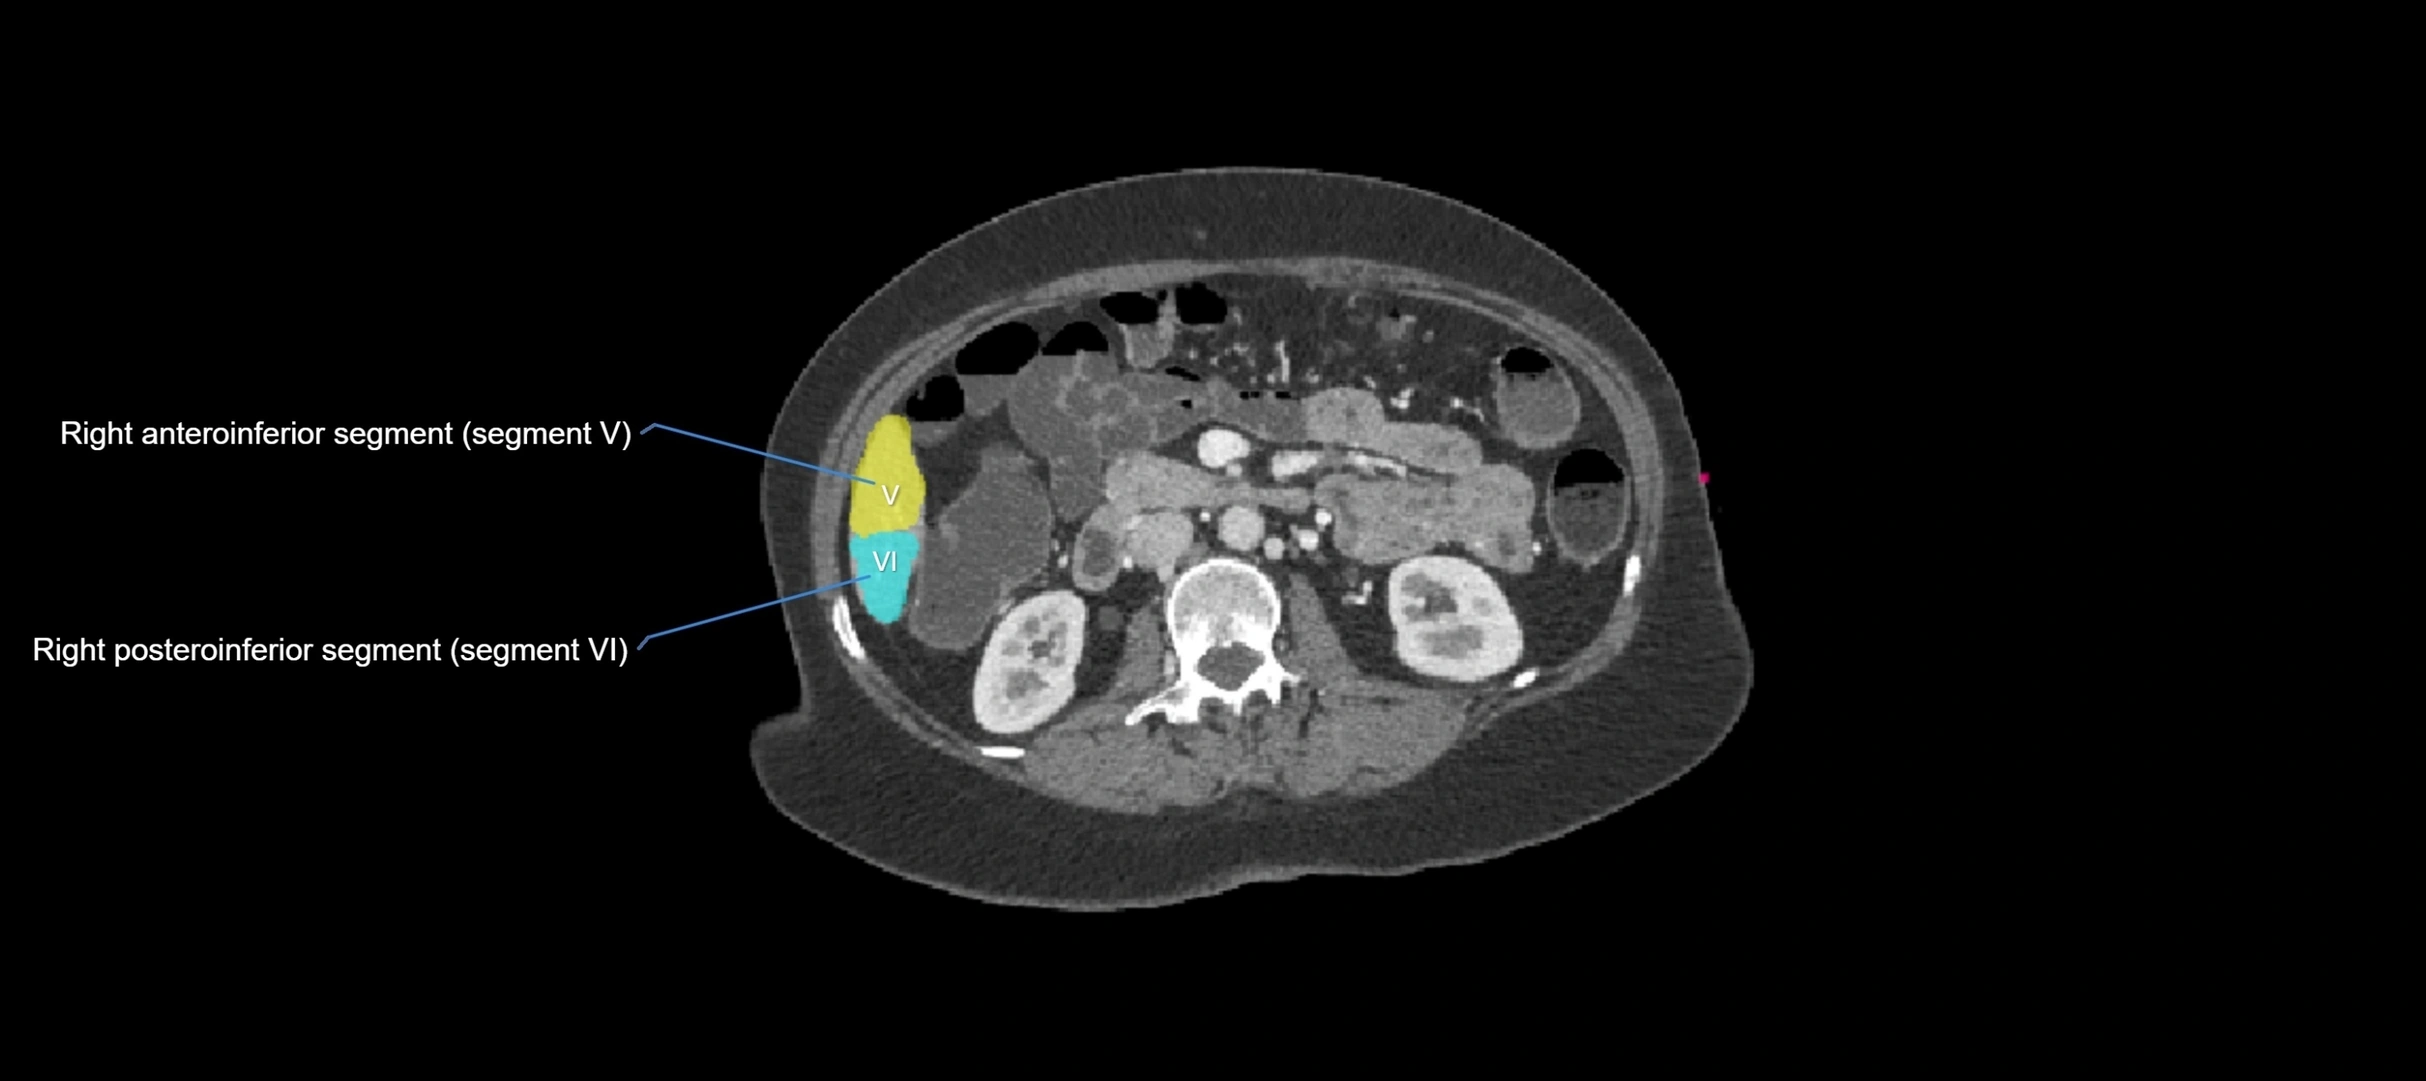

CT Appearance

CT Pre-Contrast:

• Caudate lobe appears as a soft-tissue density, isodense to the rest of the liver

• Enlargement may be appreciated in cirrhosis or Budd–Chiari syndrome

CT Post-Contrast:

• Homogeneous enhancement in the portal venous phase, similar to rest of liver

• Independent venous drainage into the IVC may be visualized

• Lesions follow characteristic CT enhancement patterns (HCC: arterial hyperenhancement with washout; hemangiomas: peripheral nodular enhancement with centripetal fill-in)

CT Venous Phase (functional significance):

• Caudate lobe often enhances relatively more than other lobes in Budd–Chiari syndrome, due to preserved venous outflow

CT Image

image